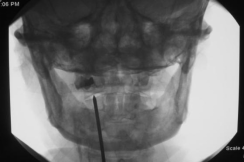

3.微创治疗:阻滞疗法(枕神经阻滞C2背根神经节阻滞)、射频治疗(C2背根神经节脉冲射频C3脊神经后支射频枕大小神经射频)和电刺激治疗周围电刺激术脊髓电刺激术),听到微创治疗不要紧张,都是局部麻醉,在颈部打个小针就可以了。